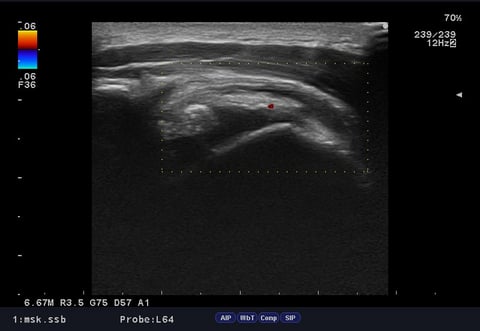

そのため、エコー(超音波)検査を実施したところ、

**腱板部に石灰の沈着(石灰陰影)**が確認され、

👉 石灰沈着性腱板炎と判断しました。